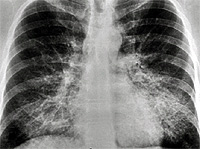

A 38 yo AAF prisoner was seen in the infirmary for a nonproductive cough. She had a history of a URI 2 months previously. Her symptoms associated with the URI had resolved except for the cough. She felt slightly feverish intermittently but her temperature was never documented. She noticed very mild fatigue and DOE that she had attributed to the URI. She was treated with a course of azithromycin without much improvement. A PPD was placed and was interpreted as negative. Because her cough persisted and she had lost 8 pounds she was referred for evaluation. Additional history revealed that her SOB and fatigue probably predated the URI, but was otherwise unremarkable. Physical exam revealed T 100.3, R 28, P 94, BP 150/96; HEENT unremarkable; Lungs with scant bibasilar rales; CV with RRR, nl S1S2, +S4, without murmurs; Extremities without clubbing, cyanosis, or edema. Laboratory data: Hct 41.2, LDH 943; ABG- 7.48/32/58; PFTs: FVC 2.62 L (71% predicted); FEV1 2.23 L (72% predicted); TLC 3.96 L (76% predicted); and DLCO 16.2 ml/min/mmHg (57% predicted).

CXR showing bilateral lower lobe infiltrates

CT showing “crazy paving pattern in lower loges

Diagnosis: Alveolar Proteinosis